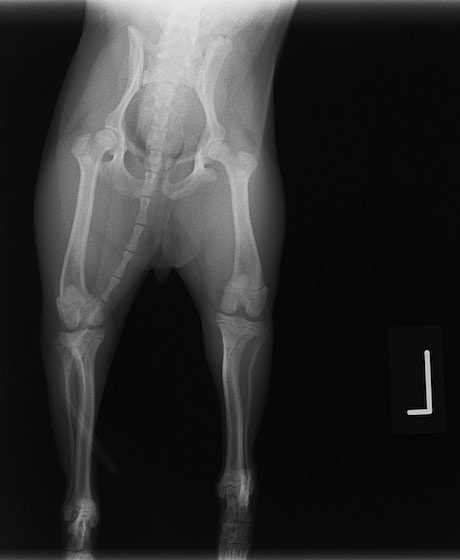

症例:交通事故による椎体脱臼

柴犬:9歳、避妊雌

交通事故直後、胸腰部に激しい疼痛、両後肢に完全麻痺を認め、シェフシェリントン徴候を呈していました。レントゲン検査において、第11-12胸椎間の脱臼が認められました。

脊髄の減圧、脊柱管の再構築・安定化を目的に、片側椎弓切除術およびMatrixMANDIBLE Plateによる椎体固定を実施しました。

隣接椎体を架橋するようにプレートを設置しました。

術後レントゲン写真